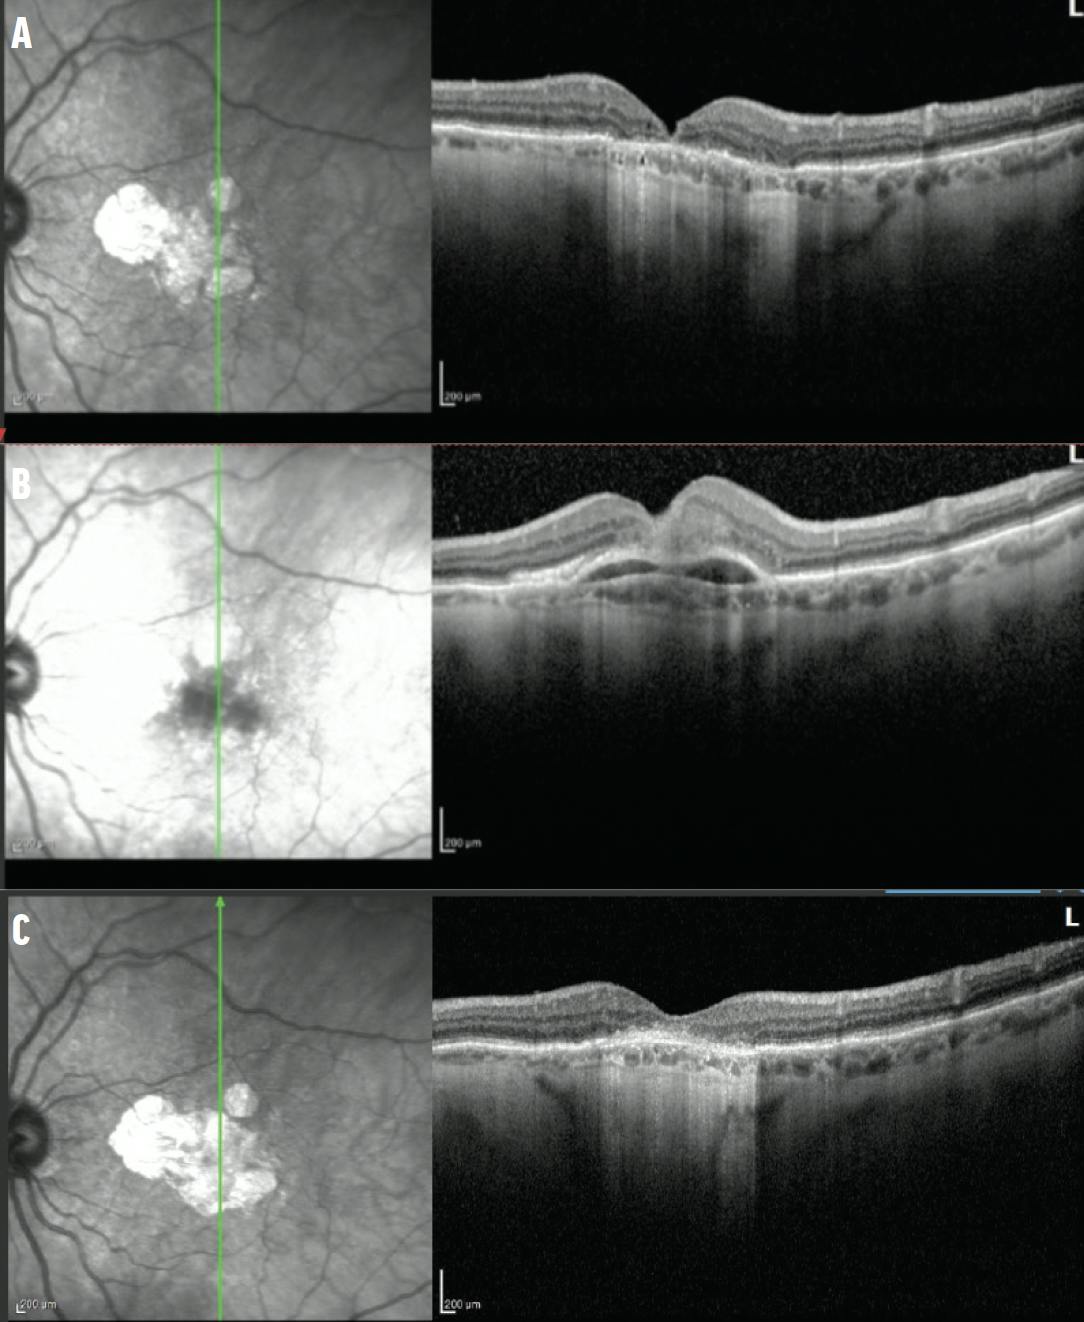

Figure 2. OCT imaging documents the transformation from dry (A) to wet (B) AMD 8 weeks after the fourth injection of pegcetacoplan. Note the fibrovascular PED with associated subretinal hemorrhage. After anti-VEGF therapy, OCT imaging shows resolution of the hemorrhage and PED (C).

An 83-year-old man presented with a 3-year history of progressive visual decline in his left eye. His past ocular history was notable for longstanding poor vision in the right eye with BCVA of counting fingers secondary to macular neovascularization (MNV). The left eye, historically with a BCVA of 20/30, had deteriorated to 20/70 at presentation. The anterior segment examination was unremarkable. Indirect ophthalmoscopy revealed retinal pigment epithelium (RPE) changes in each eye. Imaging studies, including red-free imaging, OCT, and fundus autofluorescence (FAF), demonstrated significant GA progression in the left eye (Figure 1). Given the progression, intravitreal pegcetacoplan therapy was initiated in the left eye and administered every 8 weeks. Eight weeks after the fourth injection, the patient’s VA worsened to 20/200 OS with findings of subretinal hemorrhage and pigment epithelial detachment (PED; Figure 2). There was no evidence of exudative changes at the previous visit. Pegcetacoplan was discontinued, and anti-VEGF therapy was started. While the PED and hemorrhage resolved, the BCVA remained at 20/200 with GA. The patient declined further anti-complement therapy.